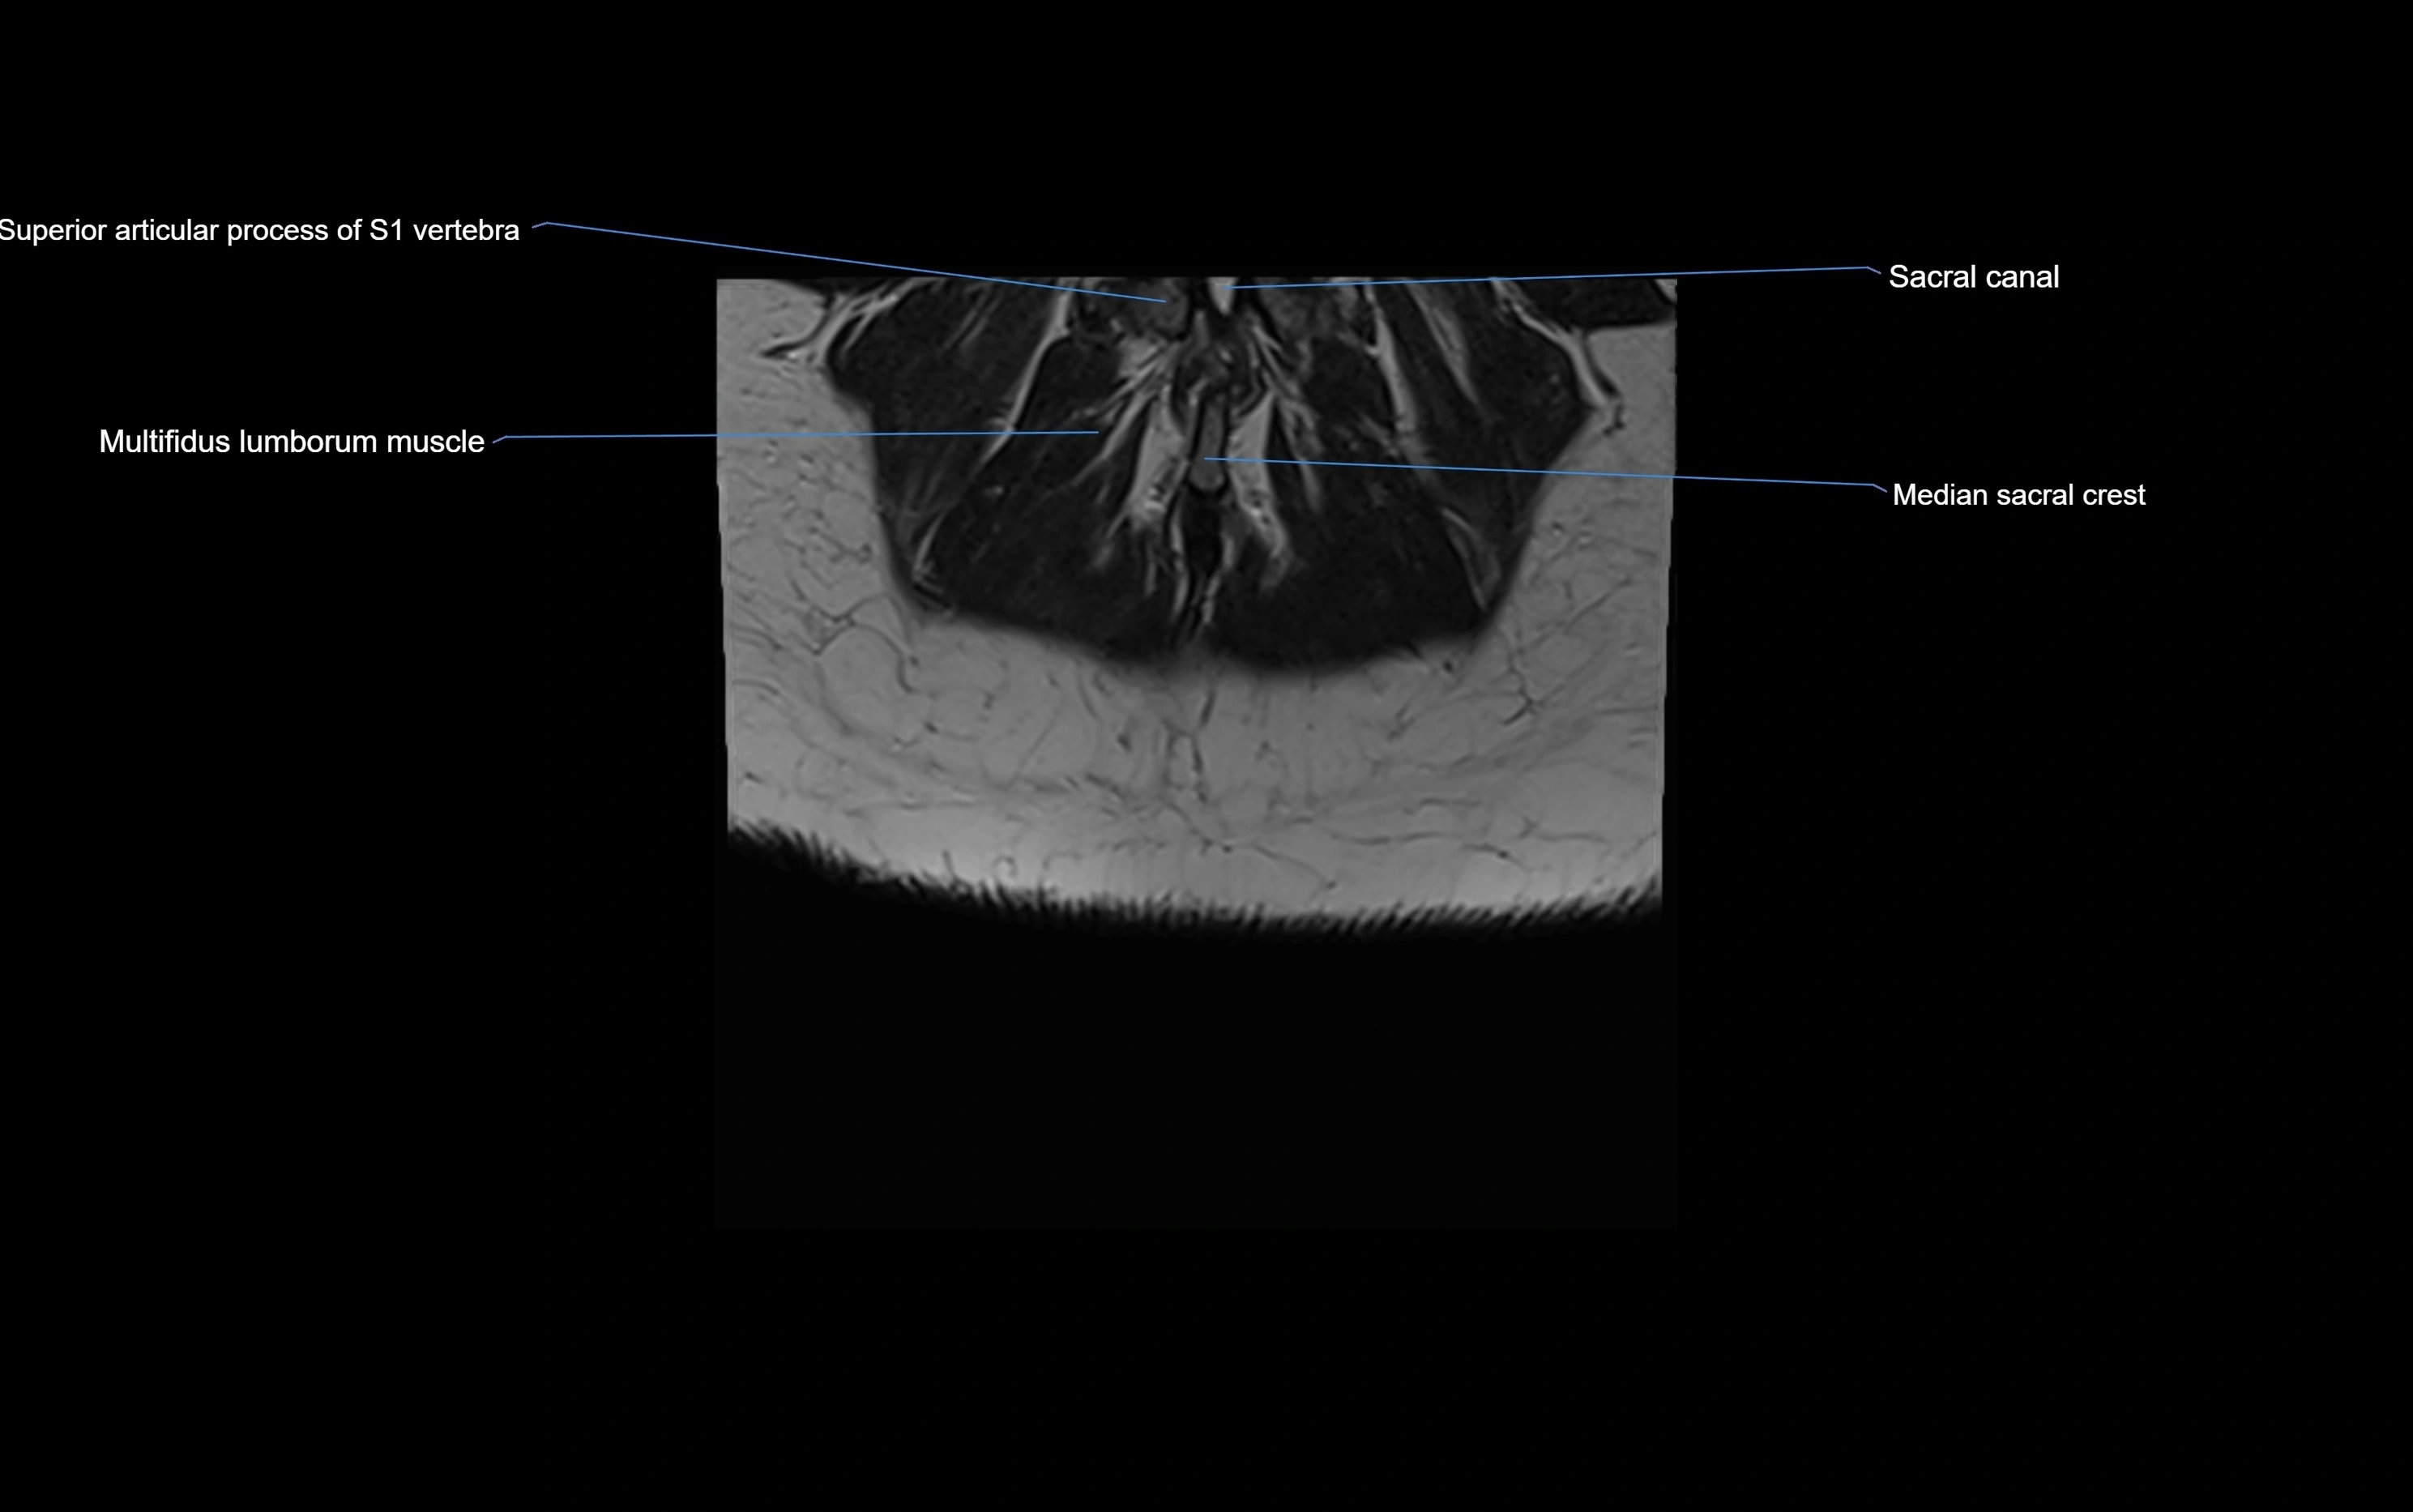

MRI image

image